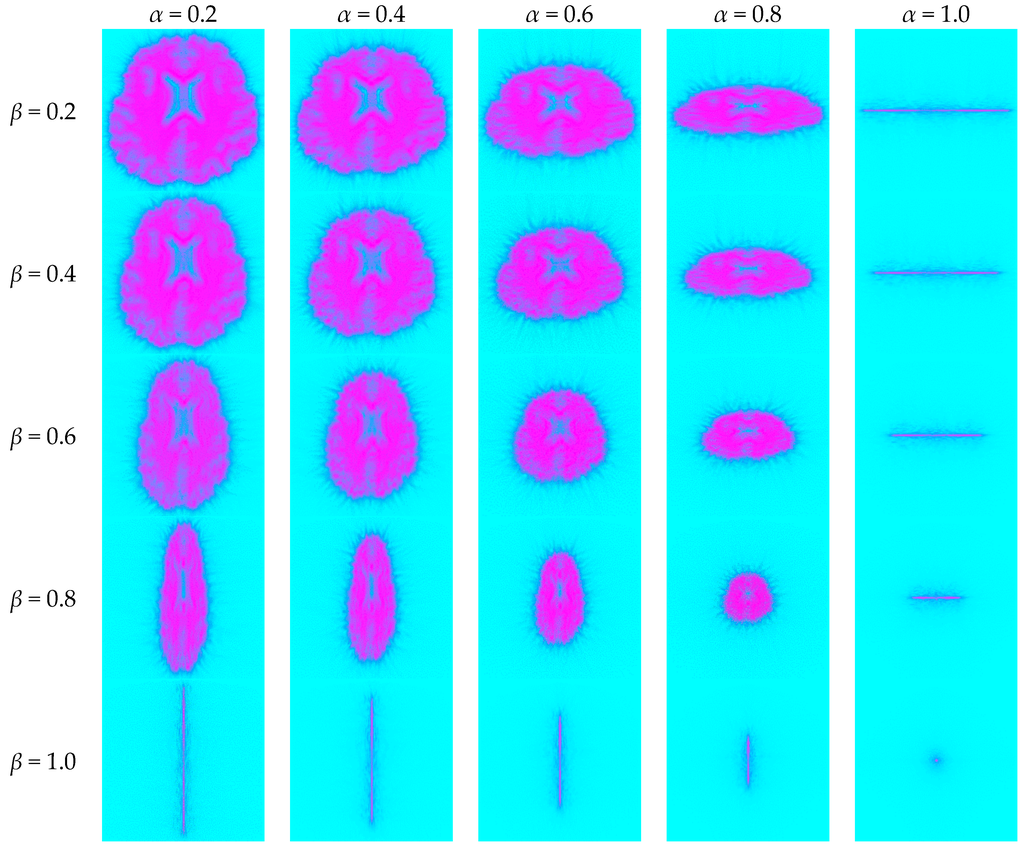

5.1. Unified Time-Frequency Domain